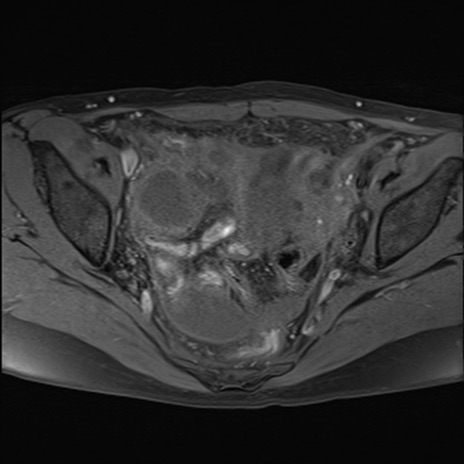

MRI(4日後)

T2WI(横断像)